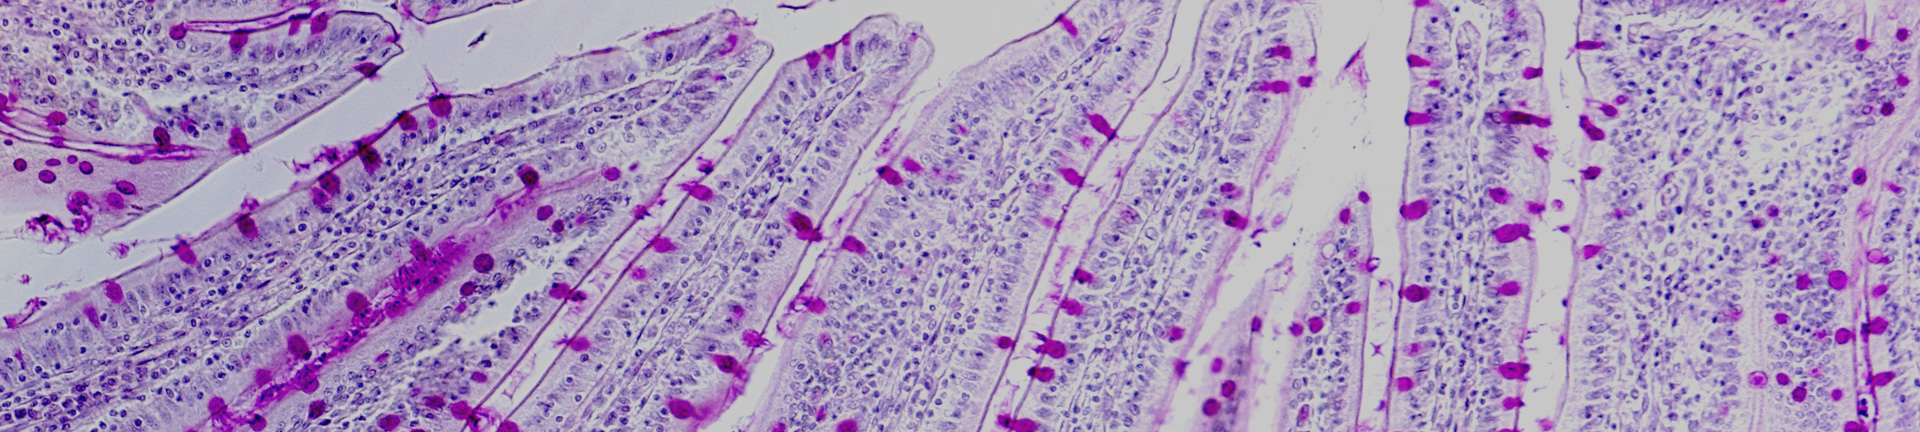

Full service histology research and teaching facility

UWA’s Histology Laboratory produces high-quality work for teaching and research purposes within UWA departments and the general scientific community. It provides a wide range of cutting-edge services, including light and electron microscopy processing and cryostat sectioning.

• Staining, including immunohistochemical staining and special stains for detection of various cellular components (an auto stainer and autocoverslipper are available for high-volume projects)